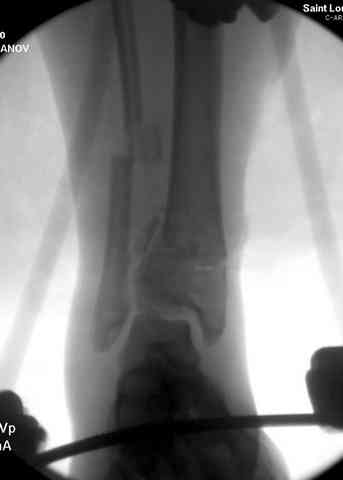

Добавлены КТ снимки. Прошу прощения за качество.

С уважением, Коваленко А.Н.

Снова приветствую вас, коллеги. К моменту вступления в обсуждение аксакалов, операция была, увы, выполнена(31.10.07.) Начали с доступа к наружной лодыжке, произвели ее фиксацию спицами, развернули кусок заднего края, наложили дистрактор, затем произвели дистракцию, фиксацию спицами дистального эпиметафиза б/бк,Рентгено-контроль. синтез наружной лодыжки 1/3пластиной. из двух коротких разрезов сформирован канал под медиальную тибиальную пластину LCP. Края ран ушиты без натяжения. Прочувствовать жесткость фиксации винтами с угловой стабильностью не удалось, поэтому дистрактор оставлен на энное время.

На представленных R-снимках не окончательный вид после остеосинтеза. Дистальная опора давила на стопу, пришлось ее сместить проксимально, в рез-те чего, она закрыла щель сустава, последние снимки не информативны.